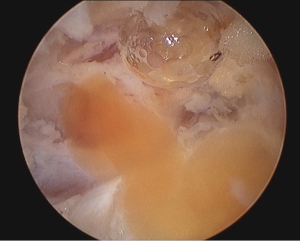

Arthroscopy revealed that the large ACL ganglion cyst was both intra-substance and extending in the posterior direction (Figures 2,3). A posteromedial portal was created to assist in visualising the ganglion from the back of the knee and to allow complete excision. The content consisted of a yellowish gelatinous material (Figure 4).